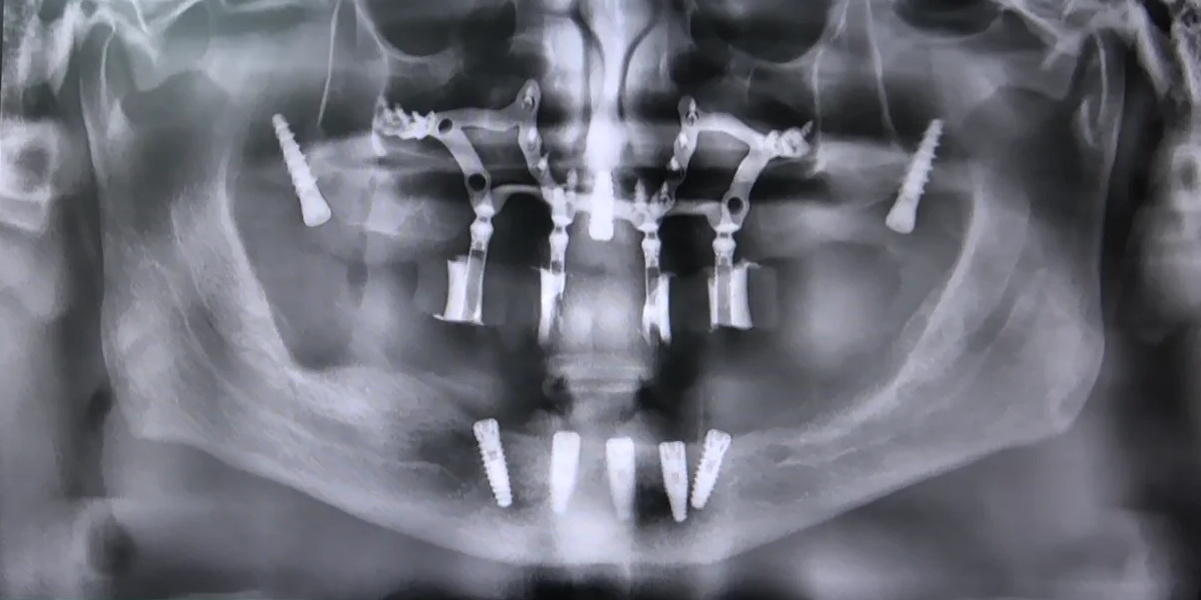

Immagini delle panoramiche prima e dopo l’intervento di implantologia dentale con tecnica del Sottoperiosteo a Griglia

Scansione con Tac Cone Beam 3D

Il primo passo consiste nell’utilizzare una Tac Cone Beam 3D per ottenere immagini dettagliate della struttura ossea del paziente. Questo tipo di scansione consente una visione tridimensionale precisa della mascella atrofica, permettendo ai dentisti di pianificare l’intervento in modo accurato.

Il file della scansione viene inviato al laboratorio, dove viene elaborato al computer per creare una griglia tridimensionale su misura per la mascella atrofica del paziente. Questa griglia sarà utilizzata come guida durante l’intervento chirurgico.